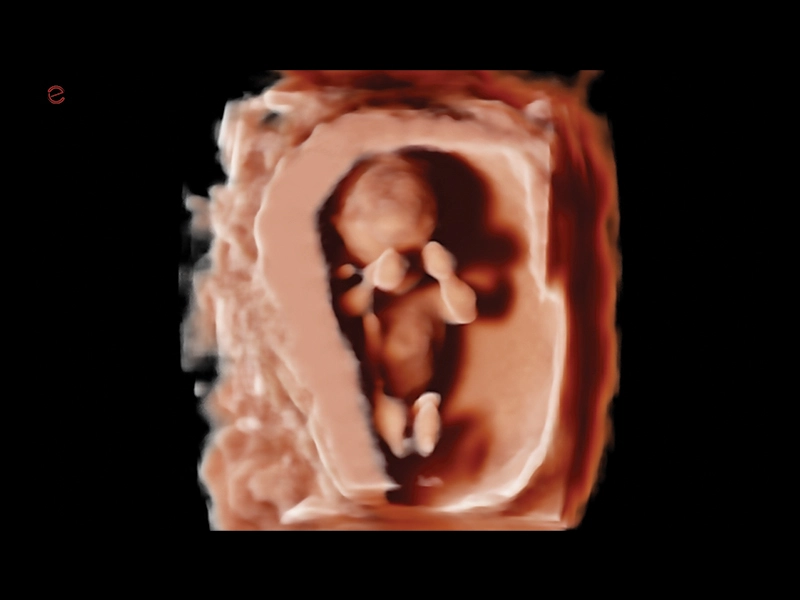

MyLab™9 Platform - Baby Face rendering in real-time with XLight

MyLab™9 Platform - Baby Face rendering in real-time with XLight